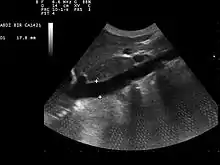

Imagerie

Dans les services de réanimation, la mesure de la variabilité respiratoire du diamètre de la veine cave inférieure par échographie permet d'évaluer la volémie, et donc de prédire la réponse à l'expansion volémique, au cours de la prise en charge d'une instabilité hémodynamique chez un patient sous ventilation mécanique[1],[2].